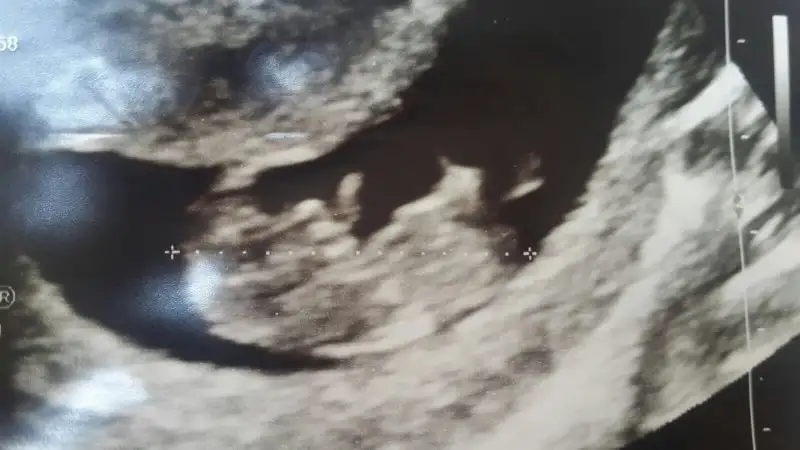

Hoş geldin canım Allah bu bebeğini kucağına almayı nasip etsin inşallahSelam hanımlar. Bende mayıs annesi olacağım inşallah. Daha önce bu başlığa yazdım mı hiç bilmiyorum2 mayıs doğum tarihi olarak görünüyor. 5+6 da kalp atışını duyduk. Şuan 12+0 dayız. 10+2 de de hareketlerini gördük kıpır kıpırdı. :) bu benim 2. Gebeliğim ilk gebeliğimde kalp atışı durduğu için kürtaj olmak zorunda kaldım nisan ayında. Bu gebeliğimde baya olaylı geçiyor.. Bulantı kusmadan bayılmalar hastanede yatmalar 2 günde bir acillik olmalar falan.. :) şuan kuvvetli bir ilaç kullanıyorum kontrol altına aldık inşallah. Herkese hayırlı gebelikler diliyorum.

Selam hanımlar. Bende mayıs annesi olacağım inşallah. Daha önce bu başlığa yazdım mı hiç bilmiyorum2 mayıs doğum tarihi olarak görünüyor. 5+6 da kalp atışını duyduk. Şuan 12+0 dayız. 10+2 de de hareketlerini gördük kıpır kıpırdı. :) bu benim 2. Gebeliğim ilk gebeliğimde kalp atışı durduğu için kürtaj olmak zorunda kaldım nisan ayında. Bu gebeliğimde baya olaylı geçiyor.. Bulantı kusmadan bayılmalar hastanede yatmalar 2 günde bir acillik olmalar falan.. :) şuan kuvvetli bir ilaç kullanıyorum kontrol altına aldık inşallah. Herkese hayırlı gebelikler diliyorum. [/Qa